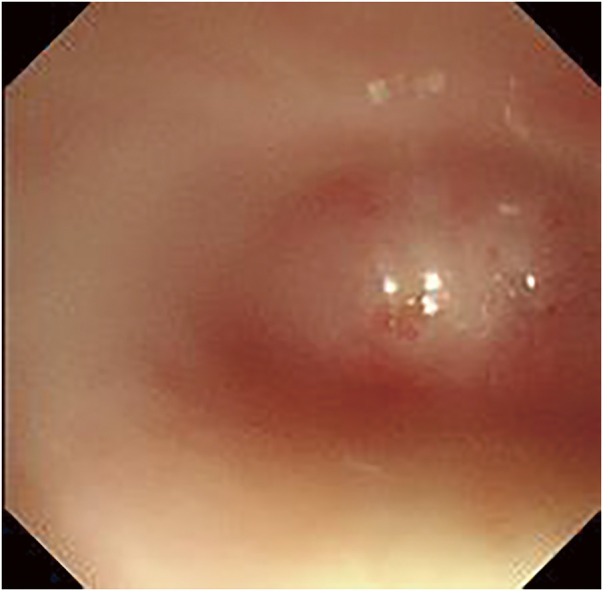

Case presentation: The patient was a 72-year-old woman. At 20 years of age, she ingested an alkali substance in a suicide attempt, leading to the development of corrosive esophagitis. Surgery was initially considered for esophageal atresia but was deemed unfeasible at the time; therefore, gastrostomy was performed instead. Subsequently, for over 50 years, she manually chewed food and inserted it into her gastric tube. She was urgently transported to a nearby hospital after her general condition deteriorated due to an influenza infection. During hospitalization, her nutritional intake was reassessed, and given her strong desire for oral intake, she was referred to our hospital for surgical treatment. Her gastric mucosa was intact, and imaging revealed mild mediastinal inflammation and fibrosis, rendering esophageal resection and reconstruction feasible. Considering surgical invasiveness, we opted for a mediastinoscopic esophagectomy and performed posterior mediastinal reconstruction using a gastric tube with a cervical hand-sewn anastomosis. The patient recovered without any complications and was discharged. Although postoperative aspiration and swallowing disorders were anticipated, the patient experienced none, likely because her unique self-feeding method preserved the functions of her masticatory and swallowing muscles.